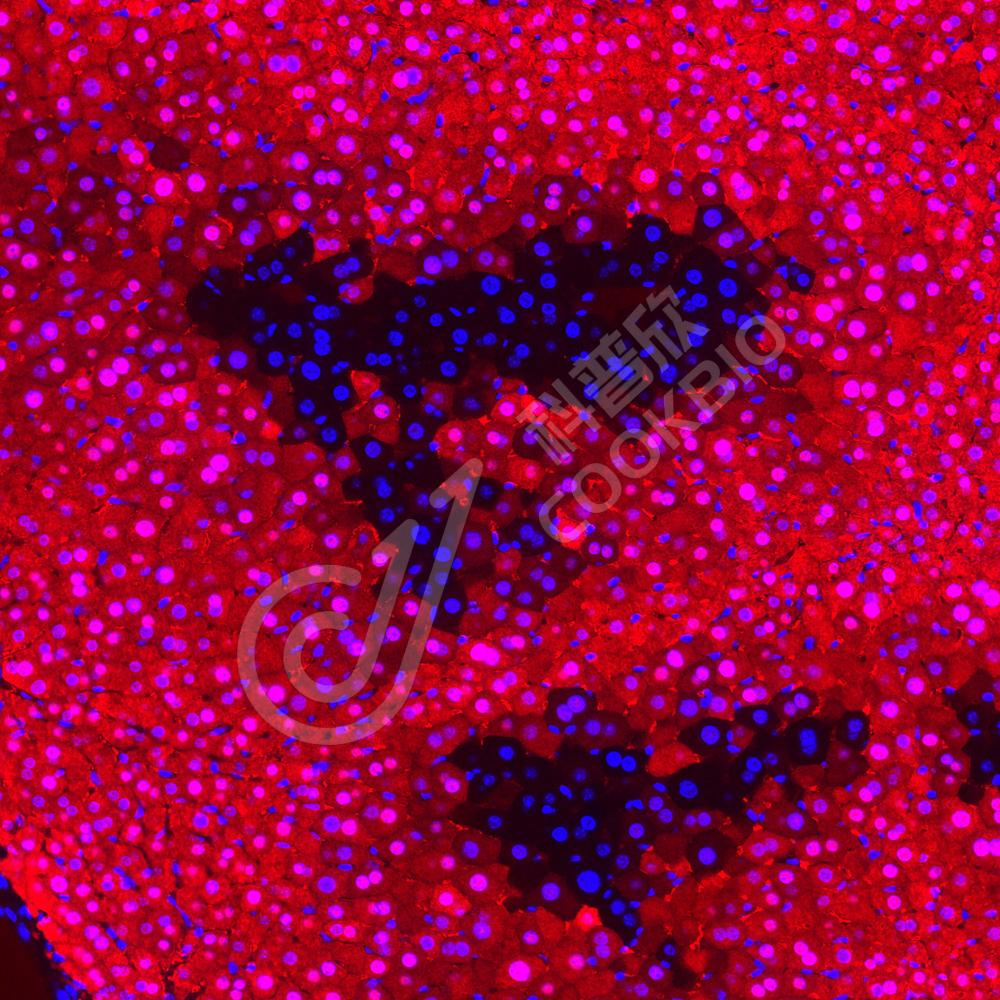

IF检测CBS蛋白(货号 K1335382)(红色).

样品: 大鼠脑, 4%多聚甲醛 (货号KSG1101) 固定12-24小时.

抗原修复: Tris-EDTA抗原修复液(pH 9.0) (KSG1203), 98℃, 20分钟.

封闭: 3% BSA(货号KSGC305010)的PBS溶液, 室温孵育30分钟.

—抗: 1: 500稀释, 4℃ 孵育过夜.

二抗: Cy3标记山羊抗兔IgG (H+L) (货号KB63909), 1: 300稀释, 室温孵育1小时.